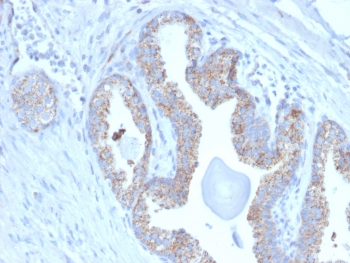

IHC staining of FFPE human prostate carcinoma with TMEPAI antibody (clone PMEPA1/2697). HIER: boil tissue sections in pH 9 10mM Tris with 1mM EDTA for 10-20 min and allow to cool before testing.